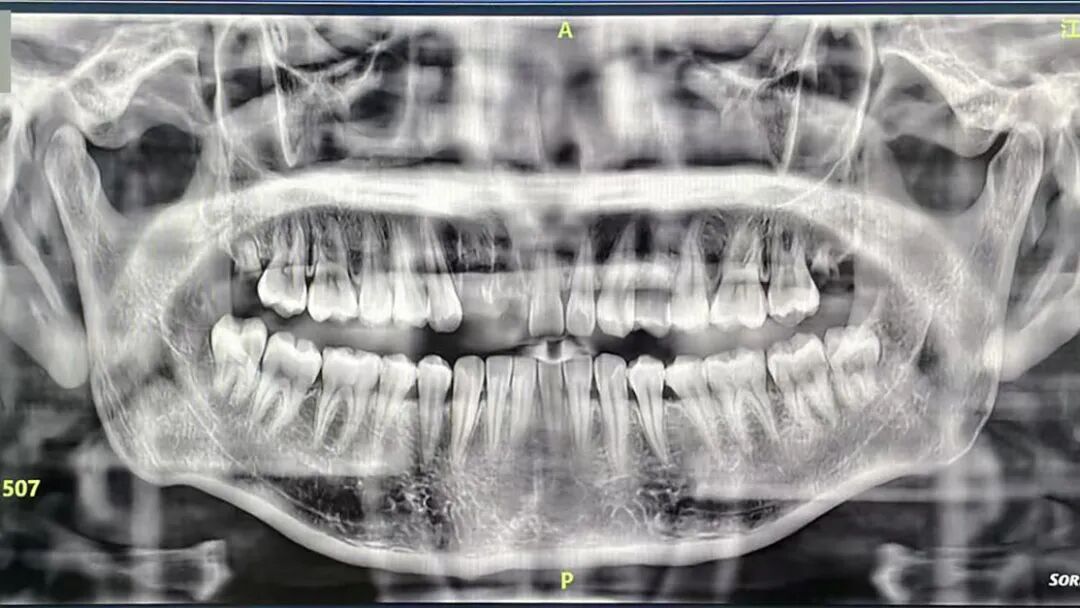

CBCT上线后,医生为他进行横断位、冠状位、矢状位全面扫描,逐层观察牙齿内部结构,终于在牙齿内部锁定病灶:根管有隐裂纹!

过去,传统牙片、全景片只能提供平面影像,像骨头密度、神经管位置这些关键信息,往往只能靠医生经验判断。

CBCT就像给口腔拍了一组“3D高清大片”,能清晰、直观地呈现口腔颌面部结构信息,为医生提供重要的诊断依据。

能够精确地定位根管的形态、数目、走向,以及牙根尖的病变情况。